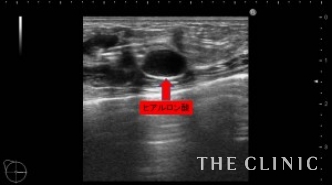

3年前にヒアルロン酸を注入された方です。ヒアルロン酸がしこりになってしまい、見た目・感触ともに無数のしこりが確認出来る状態です。画像は、皮下・乳腺組織内に注入されてしこりになったヒアルロン酸です。

ヒアルロン酸溶解注射を注入して、吸引除去します。

ヒアルロン酸注入によるしこりのエコー診断カルテ